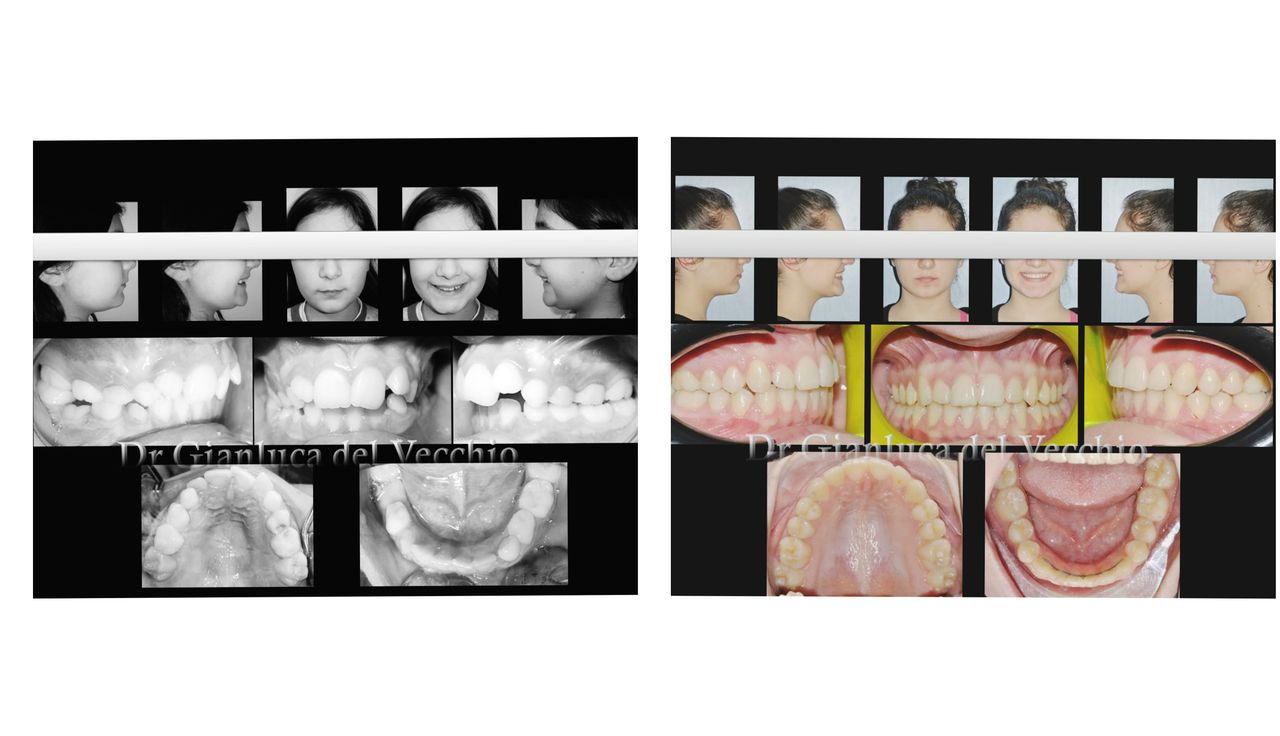

Il dottor Gianluca del Vecchio si occupa esclusivamente di ortognatodonzia, grazie anche alla collaborazione multidisciplinare di una équipe davvero entusiasmante e all’utilizzo di strumenti diagnostici e terapeutici all’avanguardia in ortognatodonzia. Particolare è la sua capacità di condurre i giovani pazienti ad affrontare, nella massima sicurezza emotiva e clinica, qualsiasi eventuale condizione di dolore derivante, ad esempio, da carie o da altre patologie, ma soprattutto di risolvere tutte quelle condizioni di “denti storti”, così spesso causa di disagio psicologico o di fenomeni deprecabili, quale il bullismo.

Queste le ragioni che consentono di trattare le malocclusioni, sia dei bambini che degli adulti, con protocolli scientificamente validati come i più veloci, affidabili e confortevoli.

Foto e video